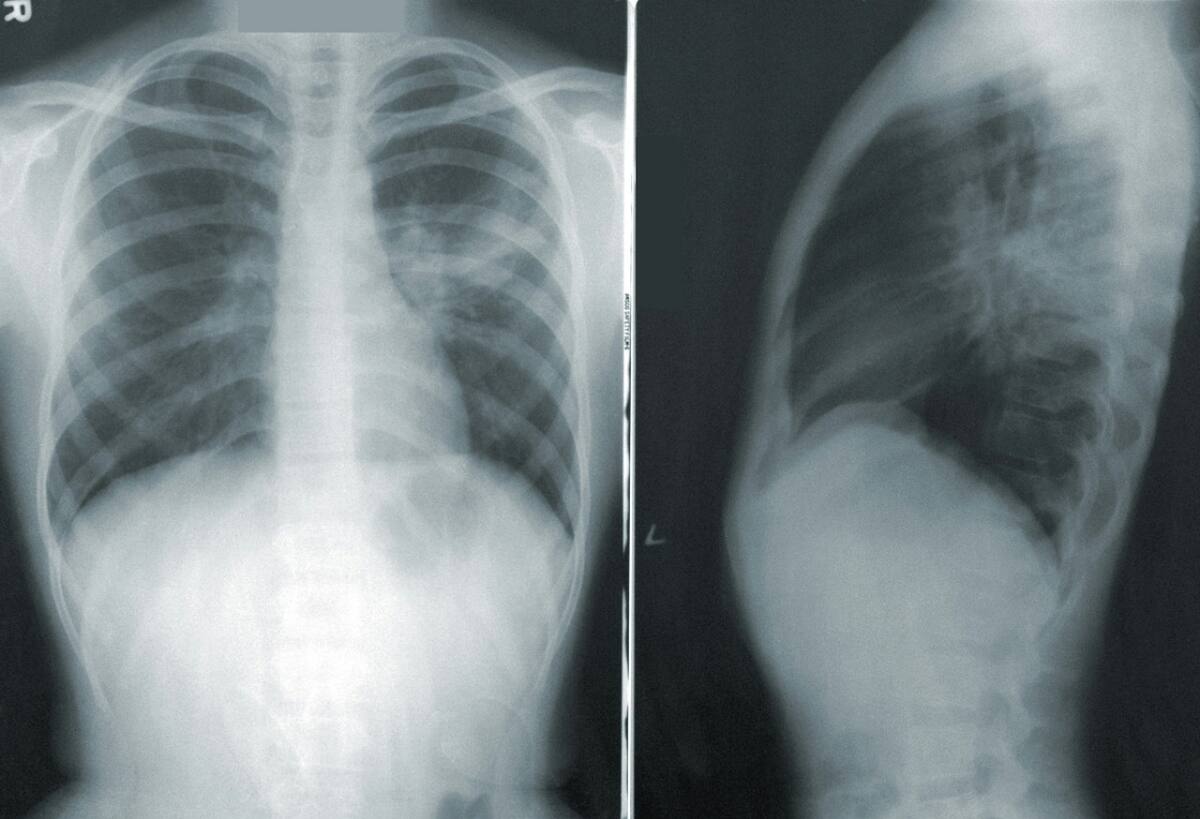

Pulmones. Foto: Freepik.